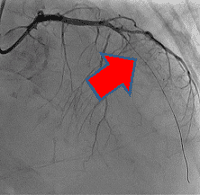

経皮的冠動脈インターベンションの一例

-

- 【1】術前

- 【2】ワイヤー通過

- 【3】ステント留置

- 【4】術後